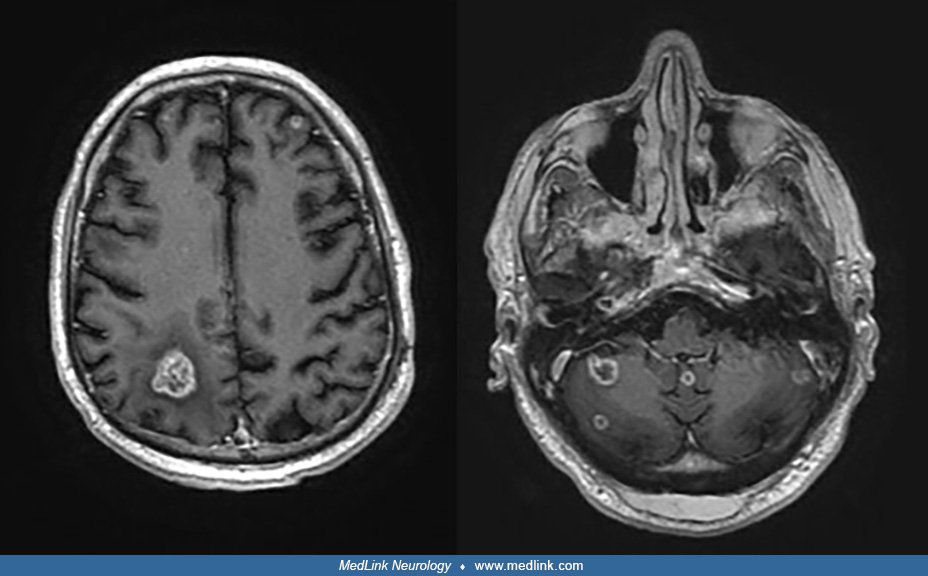

Brain metastases is the most common tumor in the brain. Common primary tumors that can metastasize to brain are: - lungs - brain - renal carcinoma - melanoma - other genitourinary tumors Reference: Bailey and Love's Short Practice of Surgery Image via: https://www.medlink.com/articles/brain-metastases